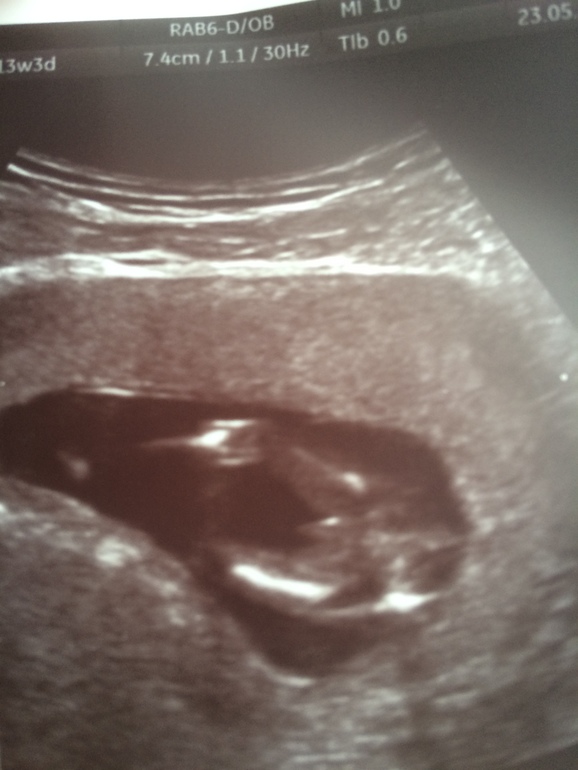

УЗИ, КТГ, доплерИ так ,второй раз подтвердили в платной больнице,что мальчик ,уже писюн торчит между ножек ,сказали уже точно ничего не отпадёт:Dмне показали и сделали фото ,сразу понятно папин сын

ктр 77 мм )все остальные данные тоже в норме )чуть обгоняем срок по М)так что если грамотный специалист и хороший аппарат то пол можно и на 11-12 недельке определить))теперь меняю кружочек на голубой цвет

фото огурчика под кат.)

Ого и правда пиписька :) вот пока вот такое не увижу не поверю что у меня мальчик :))))